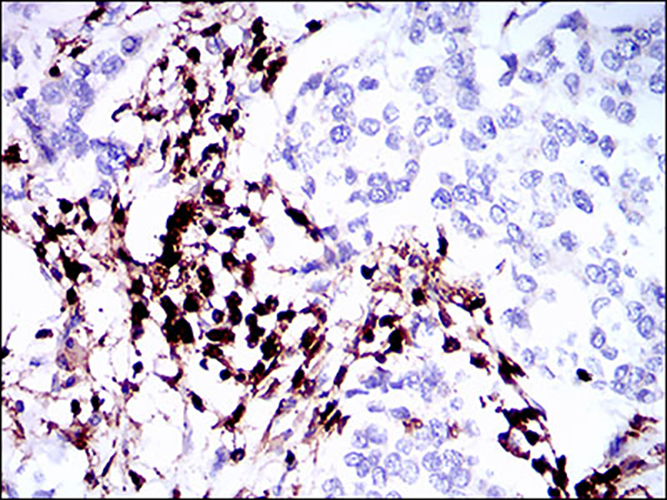

WB,IHC-P

WB: 1:500-1:1000 IHC: 1:50-1:100